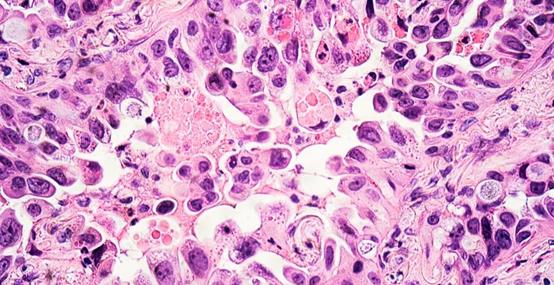

而诊断为恶性肺结节的病理类型有哪些呢?术后确诊恶性肺结节一般肺腺癌最多,占绝大多数。其次有肺鳞癌、肺转移瘤、甚至肺小细胞癌的可能,这些概率一般很小。肺腺癌的分类又包括不典型增生(即AAH,属良性病变,后期可能发展为肺腺癌,暂时放此类)、原位腺癌(即AIS,目前已认为是良性病变)、微浸润腺癌(即MIA)、浸润性腺癌(即IAC)。而浸润性腺癌又包括有贴壁型、腺泡型、乳头型、微乳头型、实体型及少见成分型等等,大多数肺腺癌不仅是一种类型,而是他们之间的各种组合形式出现,专业的病理科医生会标注清楚每种成分所占的百分比,等等很详细的信息,因为这些对临床医生非常有用,医生可以根据这些信息来判断患者的预后信息。这些信息都在术后的病理报告上显示,这个分类的逻辑关系,大家应该都清除了吧,有了这个基础知识后,继续向下看!

大家拿病理诊断的结果后,最想知道的是影不影响寿命?简单说,上述所说的良性病变,及肺腺癌的不典型增生、原位腺癌、微浸润腺癌,只要手术切除都不影响生命,切除及治愈。而对于肺鳞癌、肺小细胞癌、及浸润性腺癌会影响寿命,特别是前两者及部分后者。鳞癌及小细胞癌预后稍差。浸润性腺癌如果含有微乳头成分、实体成分预后也不佳,对于贴壁型、腺泡型、乳头型成分的Ⅰ期腺癌一般预后良好,对生命影响较小。